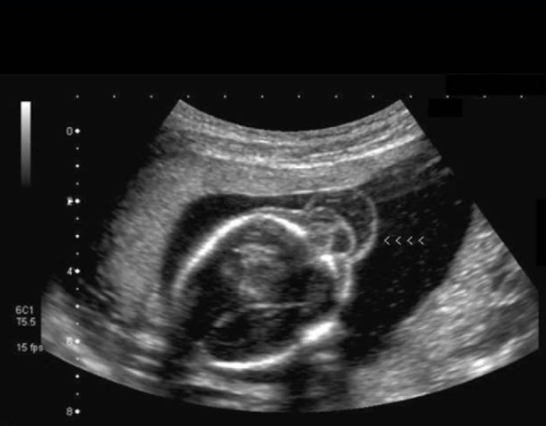

the cerebellum shows what sono sign

a) fruit salad

b) banana sign

c) lemon sign

d) string of pearls sign